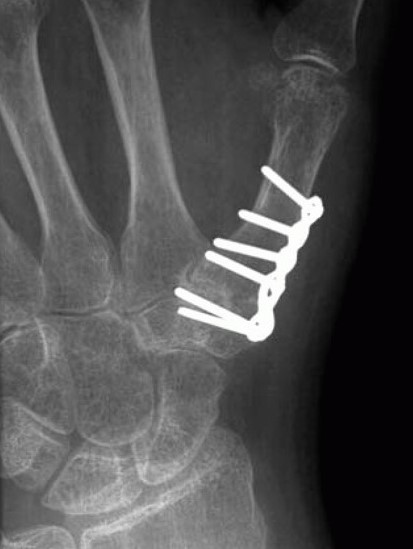

Thumb CMC Fusion

X-ray of a thumb that has been treated for basal joint arthritis with a thumb fusion. In this procedure, the joint is removed, and the ends of the joint are pressed together with a plate and screws to get them to heal together. This procedure reduces pain in the thumb, but also reduces motion.

Reproduced from Van Heest AE, Kallemeier P: Thumb Carpal Metacarpal Arthritis. J Am Acad Orthop Surg 2008; 16(3): 140-151

• One option involves fusing the bones of the joint together. This reduces pain and allows for a strong pinch; however, it will limit movement of the thumb.